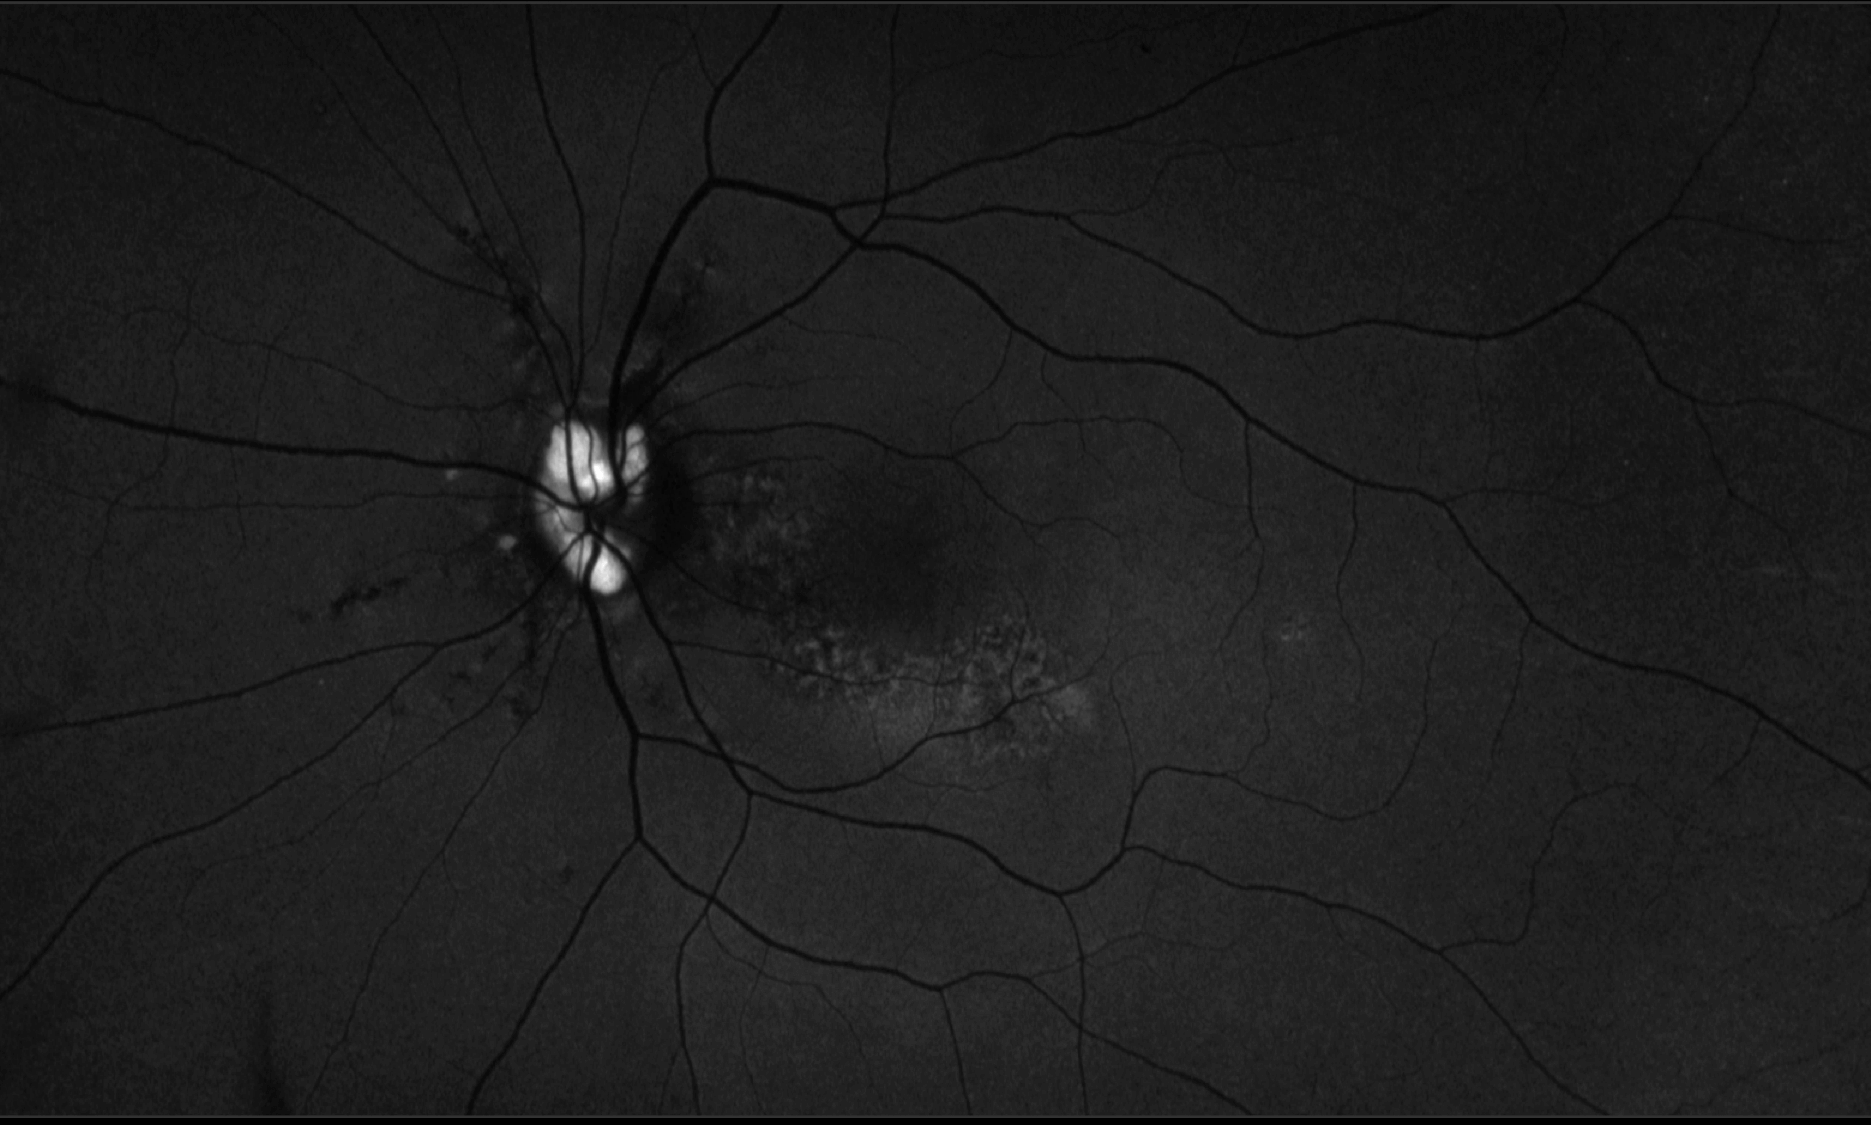

• esame del fundus per maculopatia,

• esame della tonometria oculare o pressione intraoculare e analisi della papilla del nervo ottico per monitorare progressione del glaucoma,

• stadiazione della retinopatia diabetica,

• esame della periferia retinica,